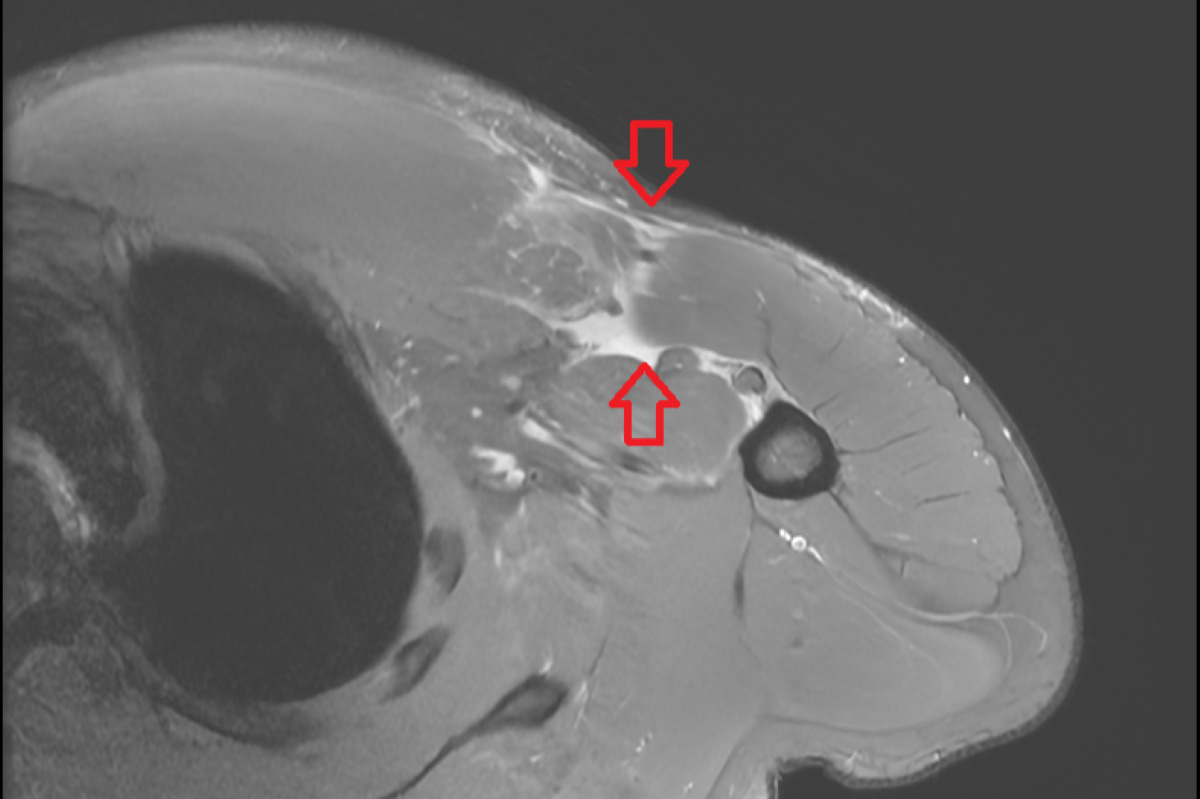

在檢查方面,醫師會先透過病史詢問與理學檢查,觀察胸型輪廓、瘀青分布、肌力變化與肌腱走向,並進一步以核磁共振檢查確認斷裂位置與程度。治療方式則需依病人狀況綜合評估,對於部分撕裂、功能需求不高的病人,可先採取保守治療,如休息、止痛藥物與復健訓練;但若為急性期完全斷裂,手術通常能帶來較佳的力量與外觀恢復。過去治療以傳統經骨縫合手術為主,需要在胸骨上鑽數個孔洞,再將斷裂的肌腱經孔洞縫合至原位。而近年則多採用縫線錨釘或皮質鈕扣等醫材進行固定,利用約4-6公分的手術傷口將斷裂的肌腱以高強度縫線重新拉回並固定在附著位置,不僅固定強度佳,也能減少對骨頭與周邊組織的破壞,有效降低術後疼痛,並幫助病人及早展開復健。李奕澄醫師補充,病人術後需依照醫師指引進行復健,整體而言,胸大肌修復後多數病人可望半年內回到運動或工作,但實際時程仍需視受傷程度與復健遵從性而定。